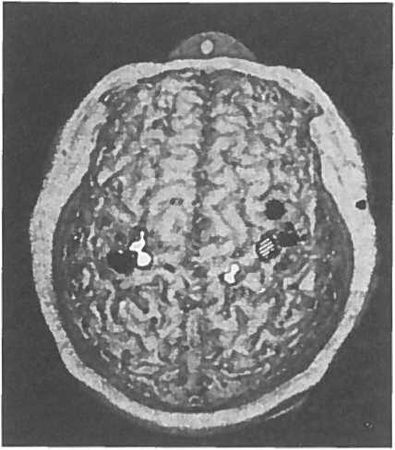

Рис. 1.3. Карта МЭГ (магнитоэнцефалограф) поверхности тела у пациента с ампутированной правой рукой. Заштрихованная область кисть, чёрные области лицо, белые области верхняя часть руки. Обратите внимание, что область, соответствующая правой кисти (заштрихованная), отсутствует в левом полушарии, но этот участок активируется, когда дотрагиваются до лица или верхней части руки